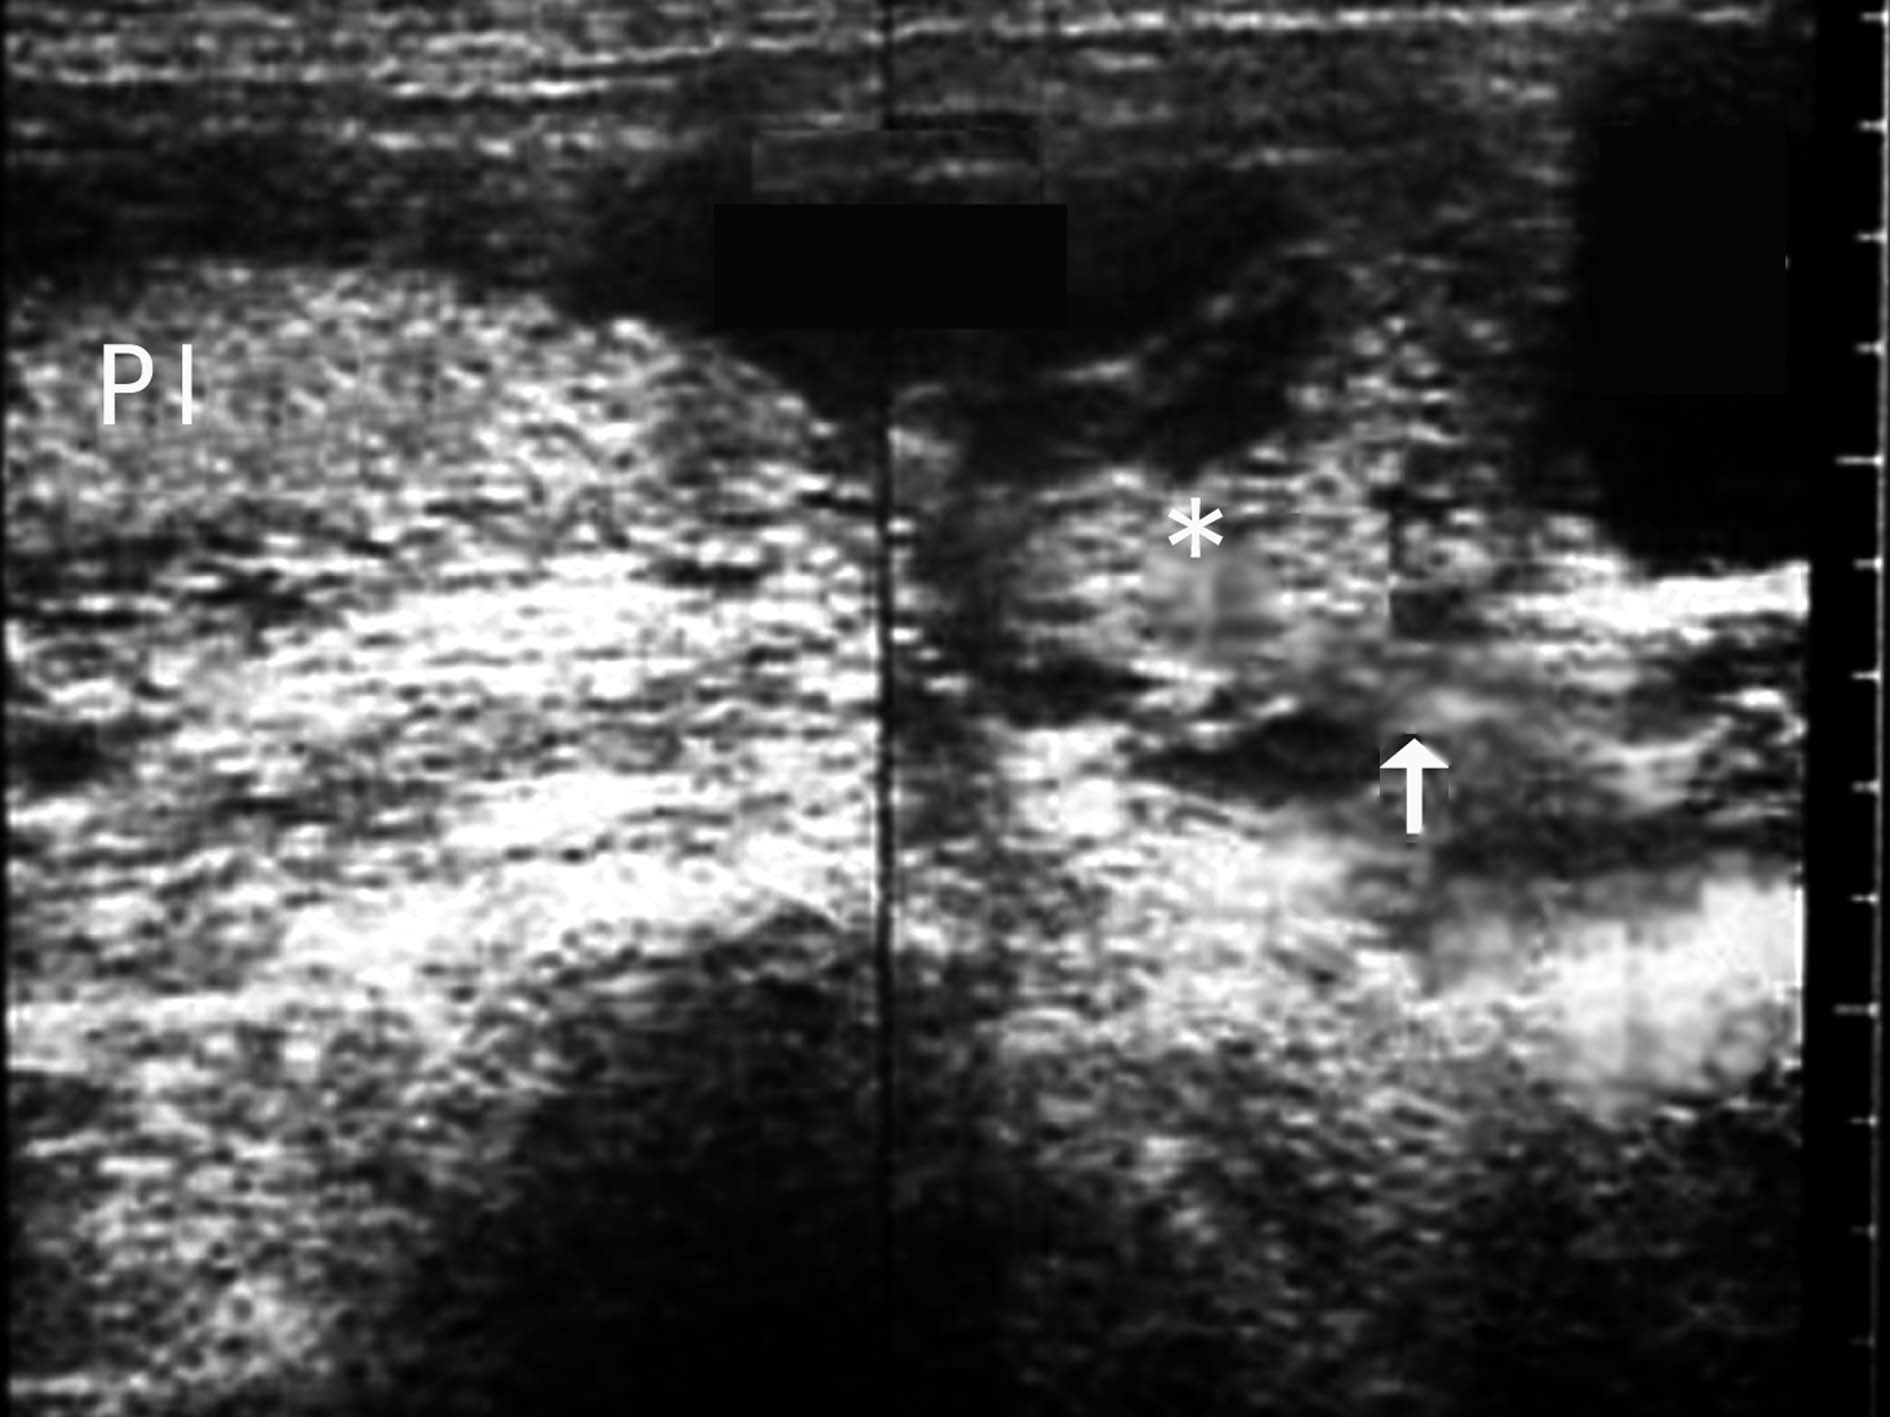

2D-US前要求孕妇充盈膀胱时要避免膀胱过度充盈。过度充盈的膀胱压迫子宫下段导致子宫颈假性延长,使原处于子宫下段的胎盘由于子宫颈的假性延长而形成假性胎盘前置(图4)。

图4膀胱不同充盈状态对胎盘位置判断的影响示意图